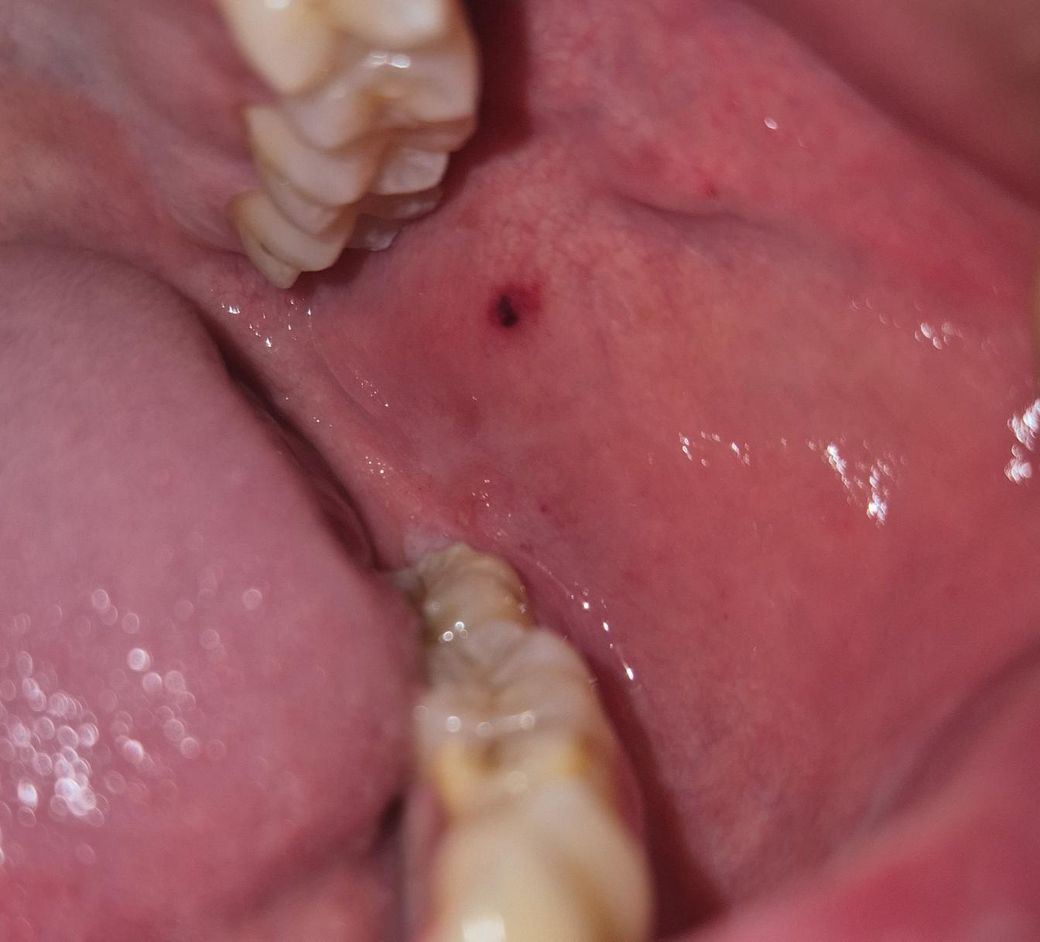

입안에 붉은 피멍울? 같은게 보입니다

오늘 보니까 저렇게 붉은 피멍울? 같은 게 보이는데 왜 저런 건가요? 통증이나 그런 건 없고요 갑자기 생겼네요 자연스레 사라지는 걸까요?

입 안 쪽에 점상 출혈이 발생한 것으로 입 안 역시 피부와 같이

모세 혈관이 많고 피부가 없어 쉽게 찢어지고 출혈이 발생할 수

있습니다. 대부분은 특이 증상 없이 시간이 지나면서 호전되어

치료가 필요한 경우는 거의 없는 것이 특징입니다